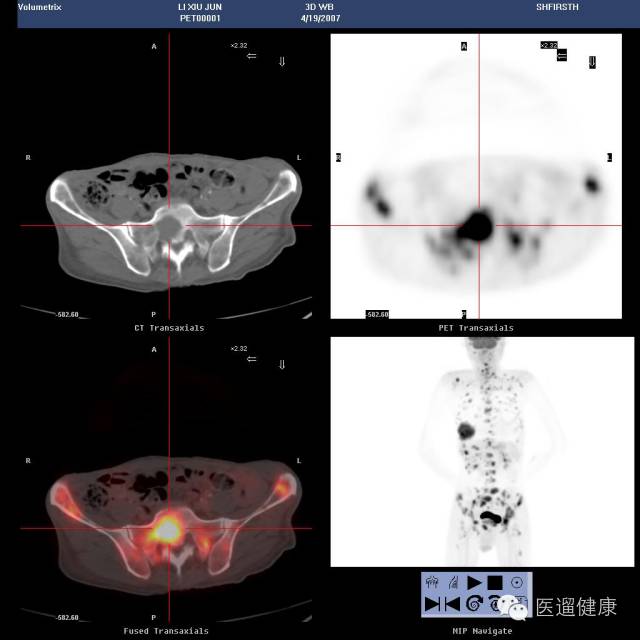

案例三

68岁男性,既往有前列腺癌病史。胸部CT:左肺下叶周围型肺癌;T9骨病灶,转移可能。

临床医生意见:

1)肺病灶是原发的,还是转移的?2)如果胸骨病灶是前列腺癌来源的骨转移灶,而肺占位是原发的话,可以对左肺占位进行手术。

困难所在:

如何鉴别胸骨病灶是前列腺癌转移来的,还是肺癌转移来的?

2013年6月24日PET/CT:

1. 盆底多发囊性病灶伴囊壁结节状葡萄糖代谢增高,考虑囊腺性肿瘤。(此后病理证实为前列腺癌)

2. 双侧髂血管旁多发淋巴结肿大,多发性骨病灶,葡萄糖代谢均增高,考虑肿瘤多发转移灶。

3. 乙状结肠结节伴葡萄糖代谢增高,考虑腺瘤可能,建议肠镜协诊。

4. 左肺下叶外基底段结节,葡萄糖代谢未见异常,建议随访。

2015-7-16PET/CT:

通过前后对比分析,判定了骨转移灶来自前列腺癌,左下肺病灶为原发性肺癌,可做肺癌切除手术。